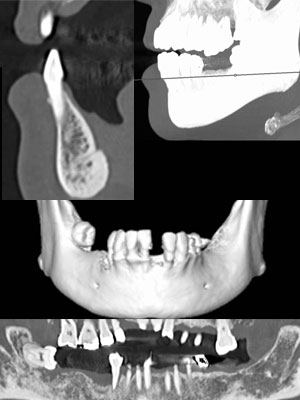

インプラントCT

• インプラント術前の委託検査を多数行っています

• DICOMデータ、実寸大プリント対応しております

• 予約TELにて、時間の確認をお願いします。

• ご紹介時には、PDFの書面に記載頂き来院ください

インプラントCT画像